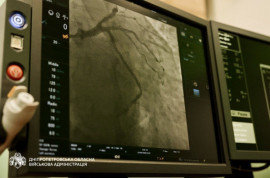

З початку 2026 року на Дніпропетровщині виконали 179 планових стентувань. Відтепер такі операції для пацієнтів є безкоштовними, як і ургентні, повідомляє Дніпропетрвоська ОВА.

Стентування застосовують при ішемічній хворобі серця, коли медикаментозне лікування не дає результату або виявлено значне звуження коронарних артерій. Операція дозволяє відновити кровотік і знизити ризик інфаркту.